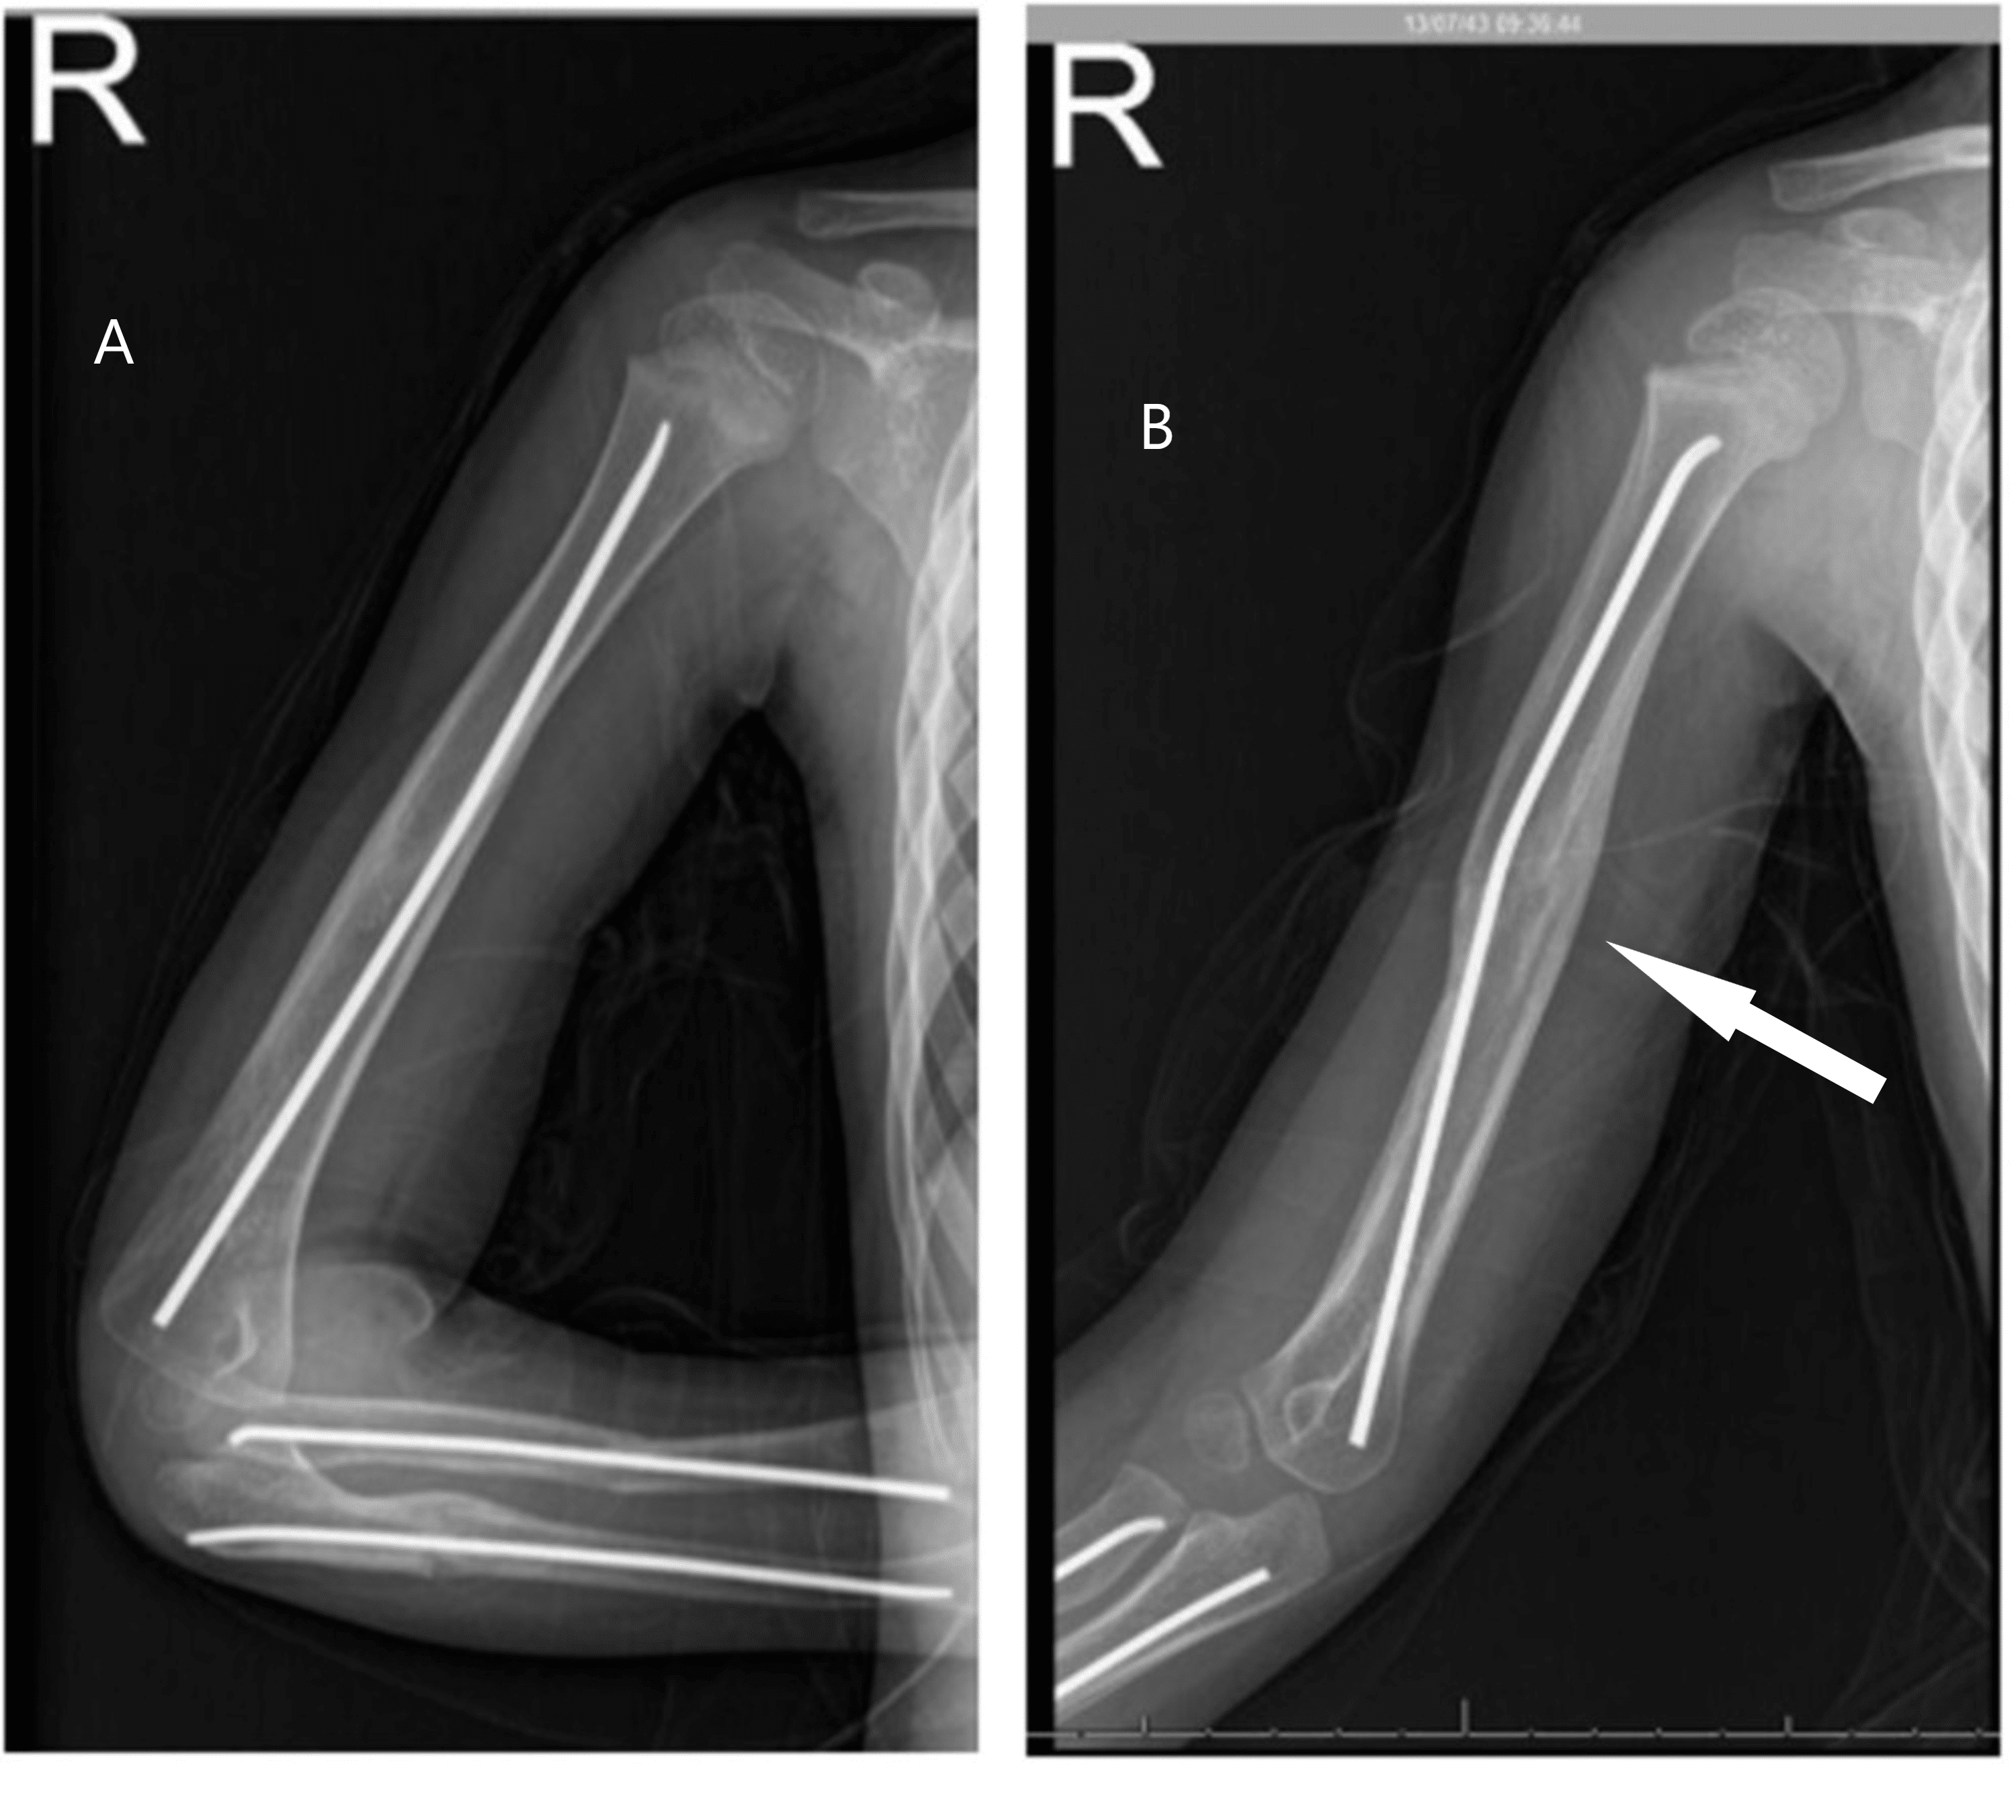

(PDF) Floating Dislocated Elbow A Variant with Articular Fracture of Floating Elbow Definition Floating elbow fractures in adults are rare and complex injuries with unpredictable outcomes. Stanitski and micheli firstly used the term “floating elbow” to describe ipsilateral humerus fracture combined with forearm. The present study was designed to. The term floating elbow was first introduced by stanitski and micheli to describe an injury pattern in children involving concomitant. The current knowledge regarding. Floating Elbow Definition.